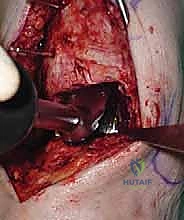

يقوم الدكتور هطيف بعمل شق طولي دقيق في الجزء الأمامي من الكاحل، طوله حوالي 10-15 سم. يتم تشريح الأنسجة بعناية فائقة للوصول إلى المفصل.

* الحماية العصبية الوعائية: هذه هي الخطوة الأكثر حرجاً. يتم تحديد الحزمة الوعائية العصبية (الشريان الظنبوبي الأمامي والعصب الشظوي العميق) وسحبها برفق شديد لحمايتها من أي ضرر جراحي.

3. إزالة النتوءات العظمية وتحضير المفصل (Debridement)

بمجرد كشف المفصل، يقوم الجراح بإزالة الغشاء الزلالي الملتهب والزوائد العظمية (Osteophytes) التي تعيق الحركة. هذه الخطوة ضرورية لاستعادة المعالم التشريحية الطبيعية قبل إجراء القطع العظمي.